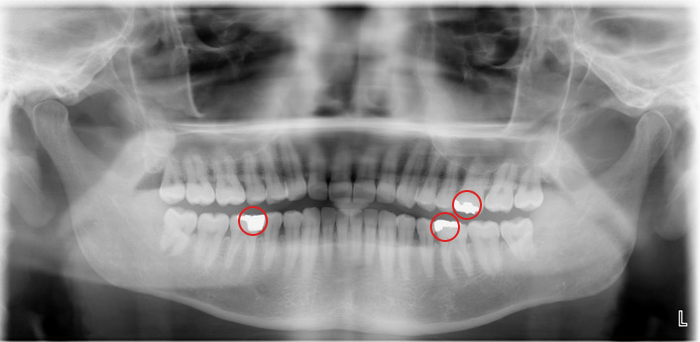

レントゲン写真

◎レントゲン写真で確認できること

● 目視しにくい歯間などの隠れ虫歯

● 虫歯の正確な箇所(発生源)や進行度

● 歯ぐきの中に埋まっている部分や歯の内側の状態

● 歯の神経や歯の根の状態

● 銀歯やインプラントの有無

● 歯ぐきの中にある親知らずの存在

● 歯周病によって歯を支える骨(歯槽骨)が吸収されていないかの確認

● 顎の骨の状態の確認

● 予想外の病気の兆候

★レントゲン写真のメリット★

● 虫歯や歯周病などの有無だけでなく、それらの進行度や歯・歯の根・顎の骨など全体の状態を網羅的に確認することができ、患者さんにとって最善の治療につなげることができる。

レントゲン写真については、実は院長自身、若かりし頃にその重要性を理解しておらず、勤務先の先輩に「ここまで明らかな場合でもレントゲン必要ですかね?」と素朴な疑問を呈してしまったことがあります。先輩いわく、「じゃあお前は歯の表面を見ただけで、虫歯の深さや歯の根の状態がわかるのか? お前はエスパーか?」と。ぐうの音も出ませんでした。確かに、虫歯の表面だけを見て、勘頼りで削る範囲を決められたら嫌ですよね…。

~おまけのミニクイズ~

野島院長には虫歯(治療済み)が何本あるでしょう? 上のレントゲン写真を見て考えてみてくださいね。

正解は、

3本(銀歯やインプラント、詰め物などは、透明感のない白色に写ります。)